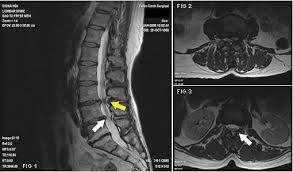

Η απλή ακτινογραφία δείχνουν κάποια ευρήματα όπως η στένωση των μεσοσπονδυλίων διαστημάτων, η δημιουργία οστεόφυτων και η απώλεια της λόρδωσης, όμως δεν στοιχειοθετεί διάγνωση της σπονδυλικής στένωσης και περισσότερο χρησιμοποιείται για να αποκλείσει άλλες παθολογίες. Η διάγνωση της σπονδυλικής στένωσης γίνεται από την μαγνητική τομογραφία (MRI) , που δείχνει με ακρίβεια το εύρος του σπονδυλικού σωλήνα και των τρημάτων, την ύπαρξη προβολής ή κήλης μεσοσπονδυλίου δίσκου, την πίεση στις νευρικές ρίζες και την υπερτροφία του ωχρού συνδέσμου. Ο συνδυασμός αξονικής τομογραφίας με μυελογραφία (CT μυελογραφία) μπορεί να χρησιμοποιηθεί σε περιπτώσεις που αντενδείκνυται η MRI, όπως σε χρήση βηματοδότη ή υλικών οστεοσύνθεσης, όμως παρά την απεικονιστική της αξία έχει ως μειονέκτημα το γεγονός πως είναι επεμβατική μέθοδος και συχνά έχει επιπλοκές όπως πονοκέφαλο, εμετούς, μηνιγγίτιδα κ.α.

Για να οριστεί διάγνωση σπονδυλικής στένωσης πρέπει η εγκάρσια επιφάνεια του να είναι λιγότερο από 100 mm2. Βέβαια, η απεικονιστική στένωση του σπονδυλικού καναλιού δεν συνεπάγεται συσχέτιση του απεικονιστικού ευρήματος με την ύπαρξη πόνου από αυτό σαν αιτία. Έρευνες έχουν δείξει πως σε άτομα άνω των 60 ετών τα ποσοστά ασυμπτωματικών ατόμων με στένωση του σπονδυλικού σωλήνα φτάνουν το 30%. Αυτό πρακτικά σημαίνει πως η ύπαρξη ενός στενωτικού καναλιού δεν χρήζει πάντα θεραπείας, καθώς η αιτία του πόνου μπορεί να είναι διαφορετική. Για αυτό τον λόγο πάντα στην διάγνωση συνεκτιμώνται το ιστορικό του ασθενούς με την κλινική και απεικονιστική του εικόνα.